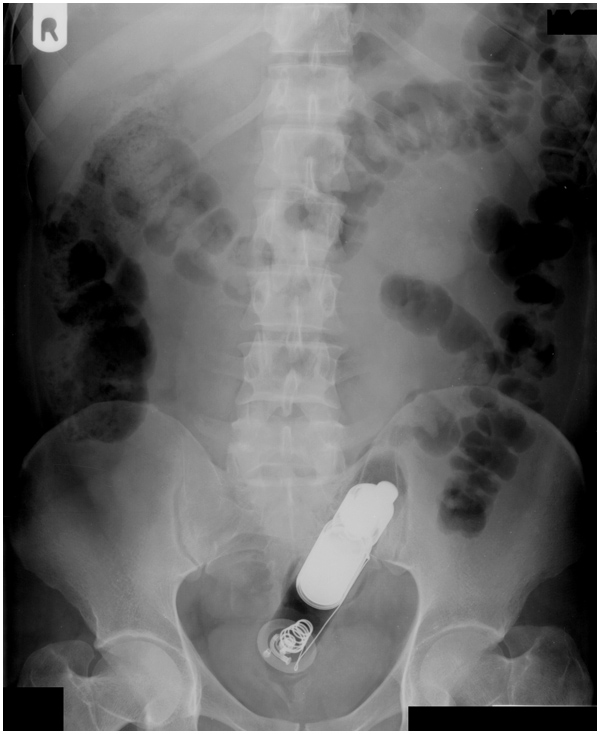

Anyway, Beagle found himself at the hospital recently, having 8 inches of “foreign” material removed from his colon….

Time to be serious. My buddy Russett was diagnosed with Colon cancer. I think in the end Stage 2, which is very manageable.

EDIT: Russett just told me stage 3b, he had cancer in 4 out of 31 lymph node biopsies.

They took out 8 inches of his colon, hardly moved the needle on the scale. I haven’t been to poker lately but I think it’s in a jar beside the TV….